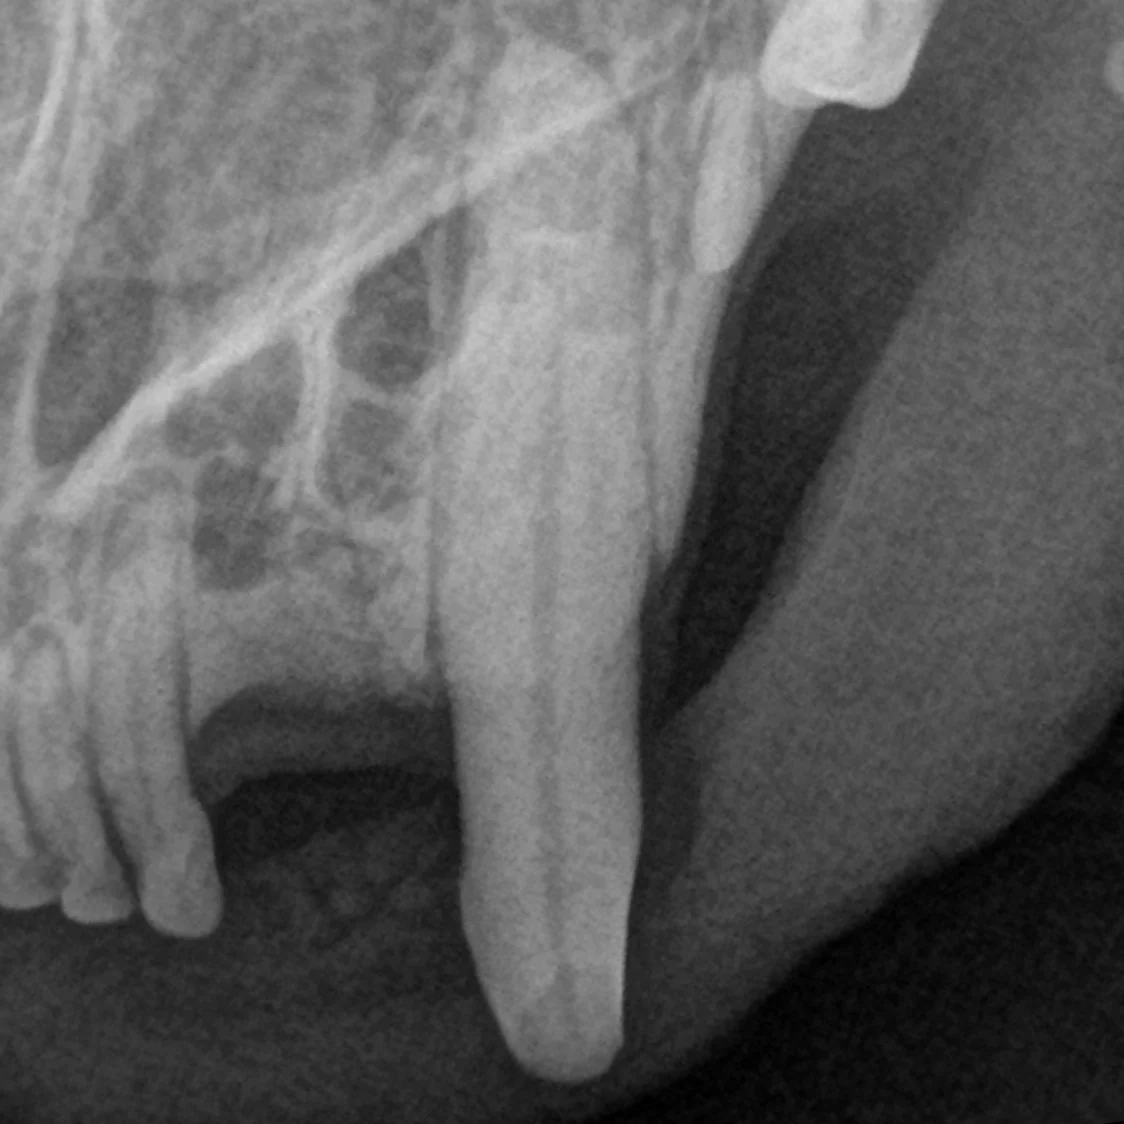

• 치아가 파절되어 신경이 노출되는 경우 신경치료 혹은 발치를 통해 통증을 해결해 줘야 합니다.

• 파절된 형태, 파절 시기, 환자의 생활 습관 등을 고려하여, 치아를 뽑지 않고 신경치료를 통해 살릴 수도 있습니다.

신경치료 전

부러진 좌측 상악 송곳니

신경치료 후

신경치료 후 레진